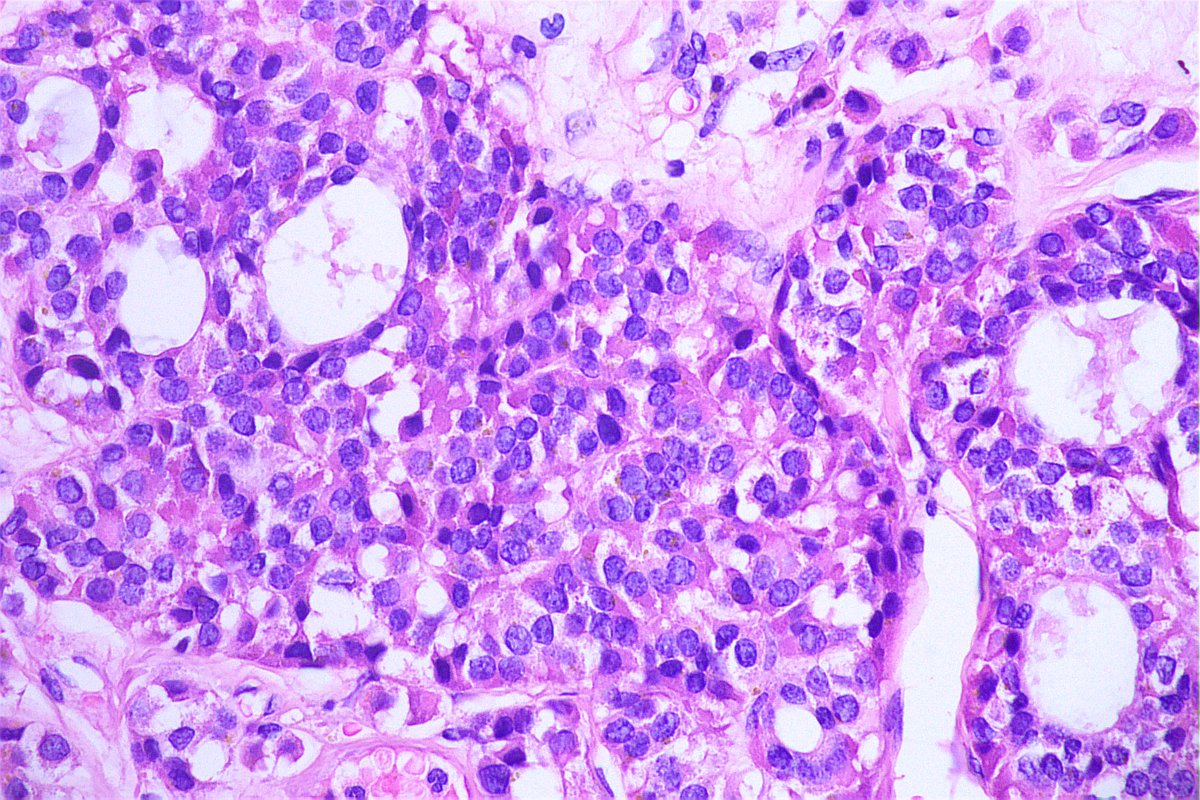

Sneak peak in classical Hodgkin Lymphoma- Large cells surrounded by mixed cell populations #APCON2022 #APCON2022PathTweet Adriana Ancer Padma Priya J Sandeep Mathur Swathi Prabhu, MD Dante shreya subramanian Meenakshi Dr Anila Sharma Archana bhat Aditya Agnihotri 🇮🇳 Olaleke Folaranmi